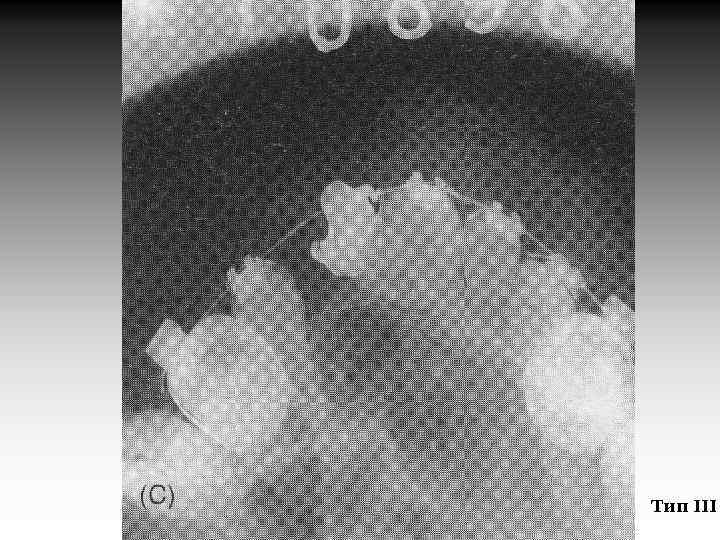

Результат ВКП находится в прямой зависимости от вида дефекта. Для наглядного сравнения после ВКП все расщелины были разделены на три группы: I. Расщелина губы и альвеолярного отростка (РГАО) II. Односторонняя расщелина губы и неба (ОРГН) III. Двусторонняя расщелина губы и неба (ДРГН) (Y. L. Jia, M. K. Fu, L. Ma. Peking University, 2006)

Тип III

Таблица 1. Результат ВКП в зависимости от прорезывания клыков и типа костного дефекта, % Вид расщелины РГАО ОРГН ДРГН 96 83 68 94 95 91 4 17 32 6 5 9 Тип Бергланда Благоприятный исход (Тип I и II) Прорезавшийся клык Непрорезавшийся клык Неблагоприятный исход (Тип III и IV) Прорезавшийся клык Непрорезавшийся клык (Y. L. Jia, M. K. Fu, L. Ma. Peking University, 2006)